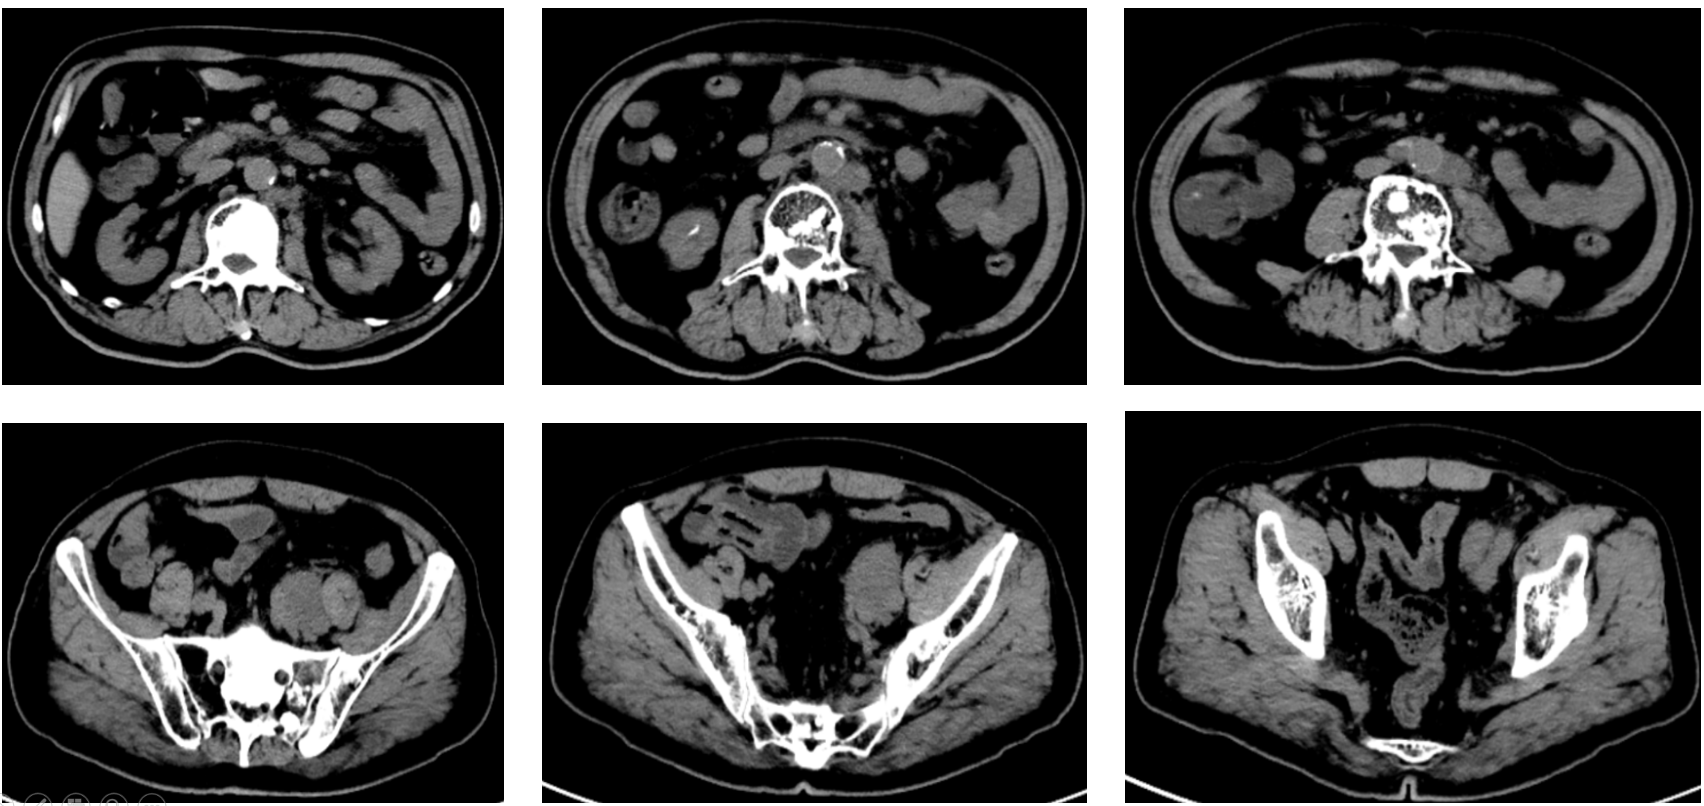

患者一月余前检查时发现右肾肿瘤,伴有肉眼血尿,尿频,尿急,尿痛,伴有腰痛,无发热等其他特殊不适,于当地医院超声检查提示右肾占位性病变,考虑肿瘤,为求进一步诊治于我院就诊,行肾脏增强CT检查提示右肾肿瘤,考虑肾透明细胞癌可能性大,肿瘤突破被膜,肾周受侵。病程中饮食睡眠欠佳,体重减轻近10kg。

右肾肿瘤 9.8cm*7.9cm

肾周受侵

肾门可见肿大淋巴结

未见明显远处转移

右肾肿瘤(肾透明细胞癌可能极大)III期 T3NxM0 IMDC 中危组。

行经腹右肾根切除术治疗。术后病理:透明细胞性肾细胞癌,肿瘤侵犯肾纤维被膜,局部紧邻肾周脂肪几肾盂,未侵犯肾窦脂肪。T3N0M1。